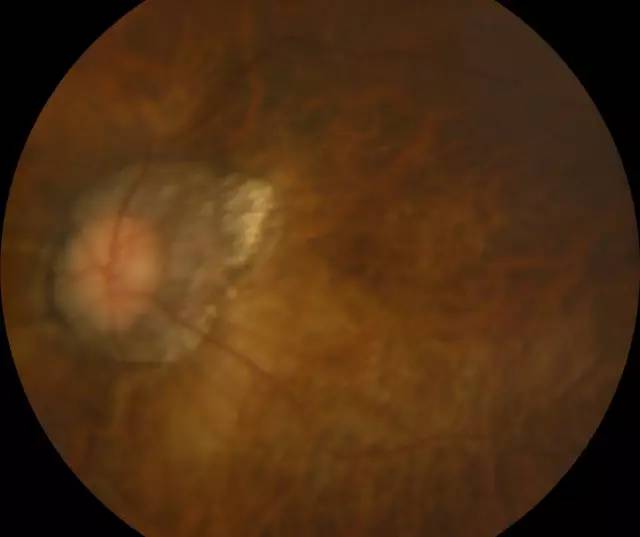

肖先生左眼术前眼底照相图

二天,赶上周末,家人陪着肖先生连忙赶到深圳6686 - 看球聊球追世界杯就来6686体育有限公司官方网站进行诊治。经过一系列检查,确诊肖先生为超高度近视裂孔性视网膜脱离,由于黄斑区视网膜全部脱离,必须要尽快做手术。